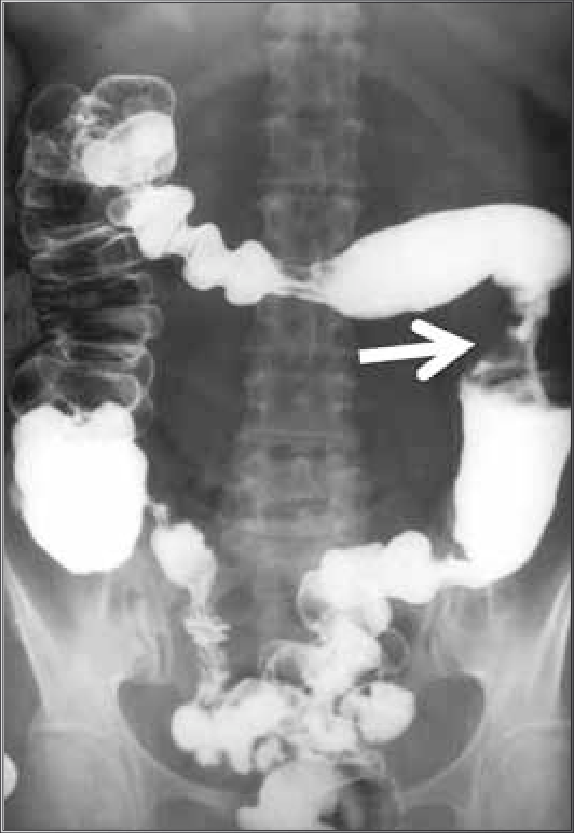

caso de tumor neuroendócrino metastático de intestino delgado com quadro característico de síndrome carcinoide. Fonte: https://doi.org/10.1590/0102-672020190001e1492

Fonte: https://doi.org/10.1590/S0100-39842007000300004